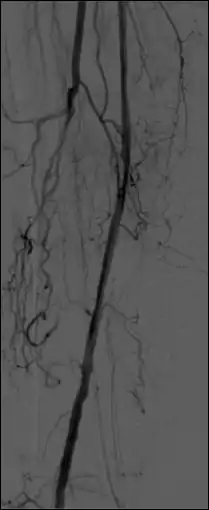

- Additional processes involve Bolus Chasing, Rotational Angiography and Volume Tomographic Angiography. Bolus Chasing[28] has been found to be particularly helpful in peripheral angiography, for example. Here, the progress of the contrast medium is tracked automatically and used to increment the table and/or XRT/image receptor movement to the next anatomical region. The subsequent set of subtraction images can then be used to construct a composite image of the peripheral vasculature. In Rotational Angiography[29], a C-arm assembly, for example, can be caused to rotate at 10 - 30 degrees per second during the imaging sequence. Subsequent dynamic display of the subtraction images can be used to generate a perceived 3D presentation so that complex relationships within the vasculature can be more readily appreciated. Volume Tomographic Angiography[30] is similar to Computed Tomography (CT) where the C-arm is rotated around the patient during the imaging sequence. The image data is subject to a volume reconstruction algorithm which permits generation of three-dimensional images of the opacified vasculature. We will consider this latter process in more detail below.